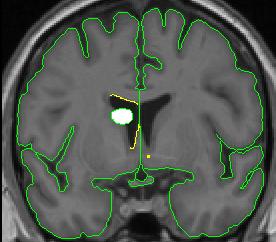

When the caudate is present two histograms are needed to define the two different borders of the ventricle.

1. Draw the first circle and create a contour for the CSF/white matter border (see above). This contour line is not a good measure of the border between the caudate and the CSF, so a separate line will need to be created for that section.

2. Clip the two ends of the CSF/white matter line where the caudate lies. For the purposes of the lateral ventricles, we consider the thalamus white matter, meaning its border with the lateral ventricle is the same contour line as the CSF/white matter line.

3. Use the "v" function to "save" the line.

4. Create a line for the CSF/caudate border. Your histogram circle should be half-way in the caudate and half-way in the CSF.

lateral ventricle 2 lateral ventricle 3

lateral ventricle 4 lateral ventricle 5

1. You may need to manually connect your "saved" contour to the new contour. By convention, in cases in which the caudate is present, include the most inferior extent of the CSF/white matter border as the lateral ventricle border, even if that necessitates drawing a short line from it to the CSF/gray matter border.